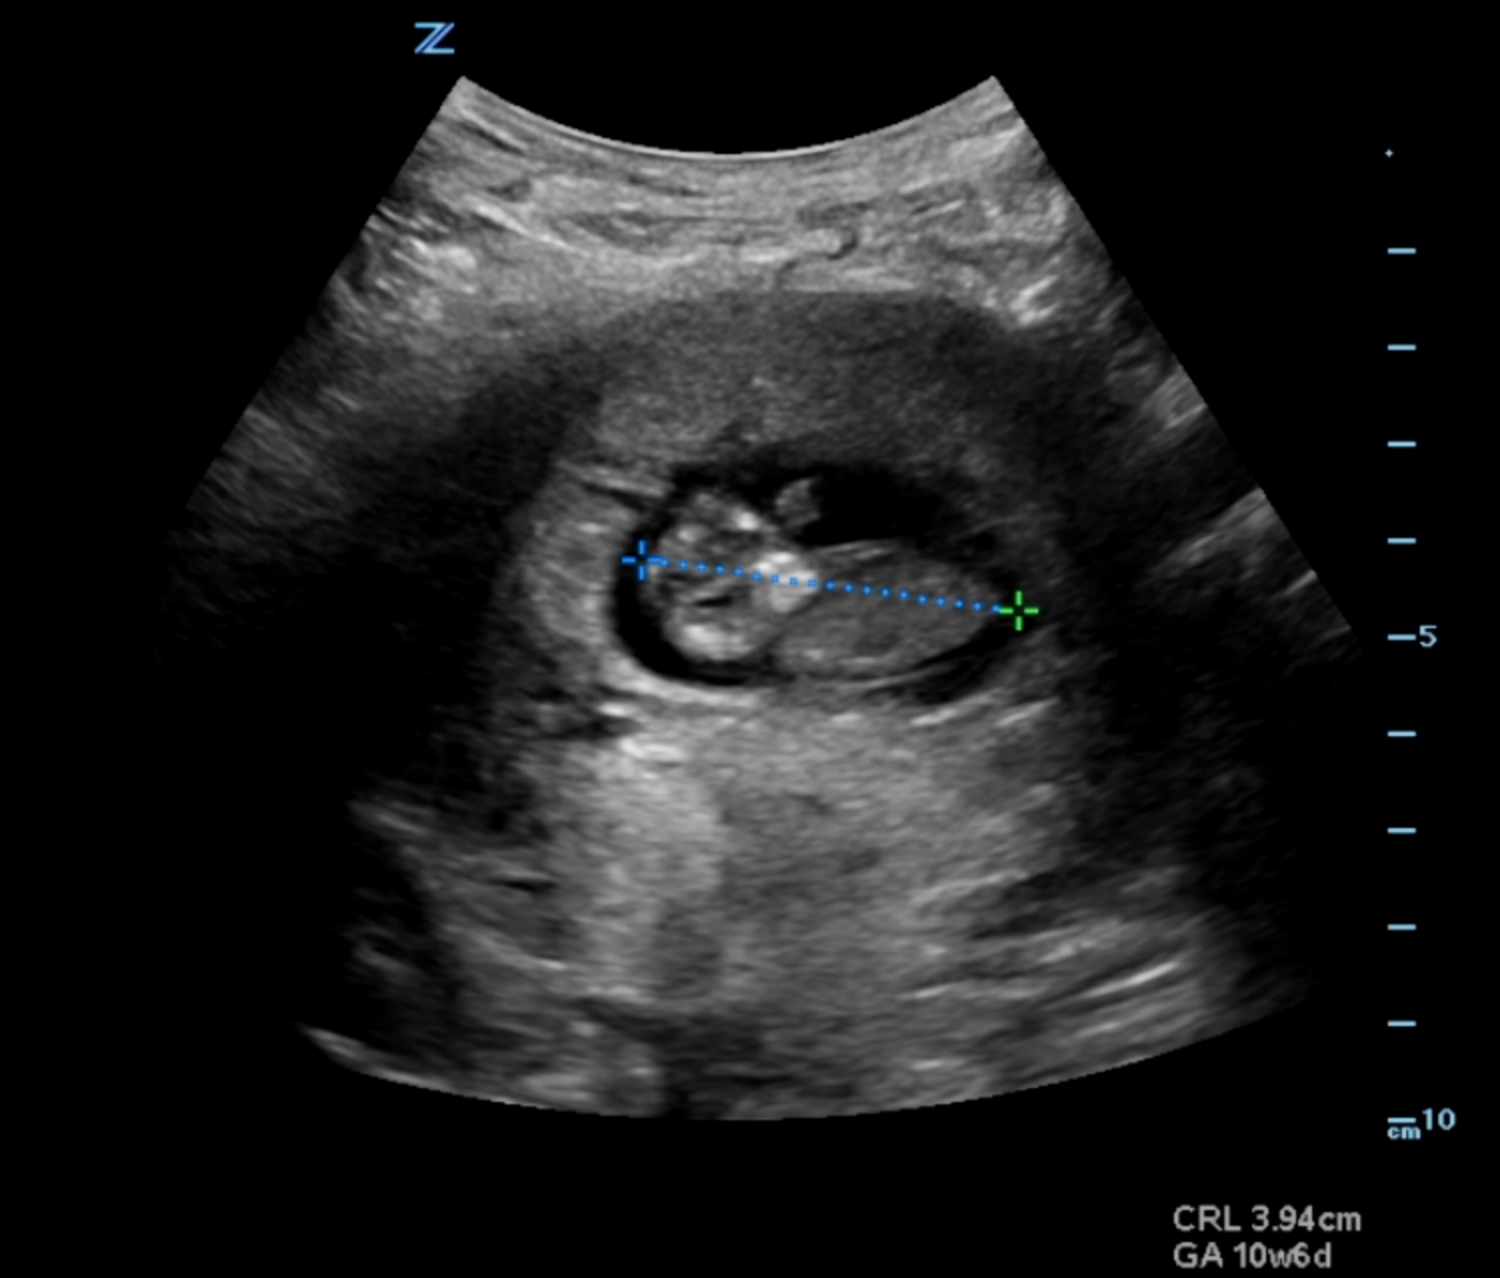

- Dating can be achieved by obtaining crown rump length when fetal pole becomes visible and then biparietal diameter when fetal skull becomes evident at the end of the first trimester.1 (Illustration 10, 11)

- Illustration 10. Transabdominal transverse view of 10-week fetus with crown rump length measurement.